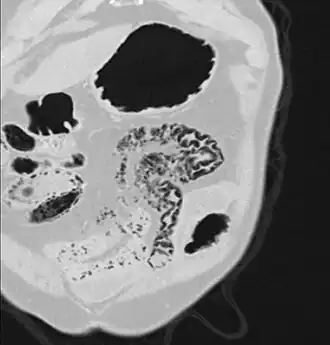

Pneumatosis intestinalis at computed tomography in intestinal ischemia. Lung window for better representation of the gas deposits in the intestinal walls. Coronal reconstruction. -

Pneumatosis intestinalis in the coronal computed tomography in lung window. It can be seen next to gas entrapment in the bowel wall and gas in the stomach wall and in numerous vessels, including the portal vein into the liver. -

Pneumatosis intestinalis in computed tomography with intestinal ischemia. Lung window for better representation of the gas deposits in the intestinal walls. - Upright AP radiograph showing gas in the wall of the small bowel in the left upper quadrant indicative of pneumatosis intestinalis.

- Coronal reformatted MDCT image showing extensive pneumatosis intestinalis in the left upper quadrant small bowel. The pneumatosis is more cystic and nodular in the small bowel in the midline and the right of midline. This patient had a relatively benign presentation without bowel ischemia and was treated conservatively.